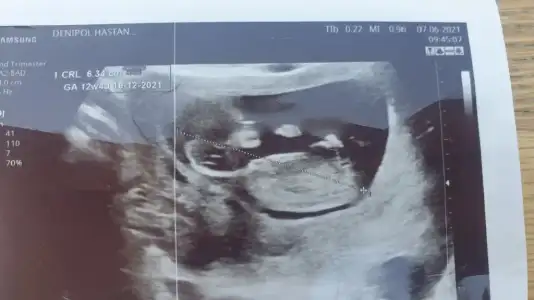

dr soylemeden siz gorun genital nub teorisi ( bebegin cinsiyeti)

Nuba göre kız mı erkek mi sizce kızlar?

Merhabalar bizimde bebeğimiz 12 haftalarda yorumlarsanız çok sevinirim Ikra meyra Ikra meyra